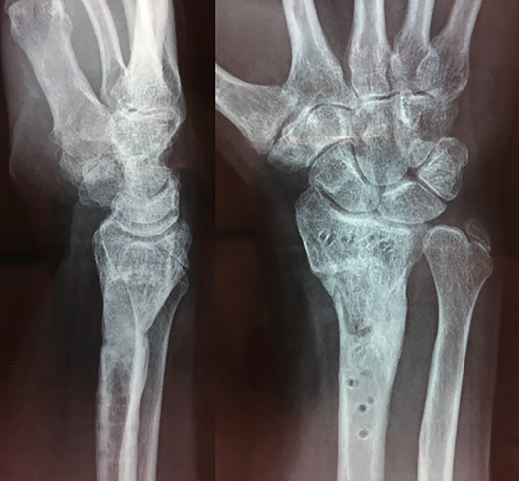

Figura 4. Aspecto final al mes de la retirada del material.

El paciente requirió extracción de la placa por tenosinovitis de los flexores al año de la segunda cirugía (Figura 4). La exploración final, al mes de la retirada del material, comprobó un balance activo de los arcos de movimiento: extensión 40°, flexión 60°, desviación radial 20°, desviación cubital 40° y pronosupinación completa. Balance muscular de 4/5, cierre completo del puño y pinza oposición completa.